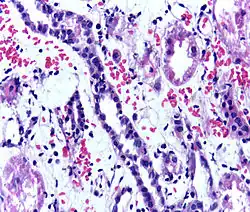

Immunosuppressant drugs are used to suppress the immune system from rejecting the donor kidney. These medicines must be taken for the rest of the recipient's life. The most common medication regimen today is a mixture of tacrolimus, mycophenolate, and prednisolone. Some recipients may instead take ciclosporin, sirolimus, or azathioprine. The risk of early rejection of the transplanted kidney is increased if corticosteroids are avoided or withdrawn after the transplantation.[66] Ciclosporin, considered a breakthrough immunosuppressive when first discovered in the 1980s, ironically causes nephrotoxicity and can result in iatrogenic damage to the newly transplanted kidney. Tacrolimus, which is a similar drug, also causes nephrotoxicity. Blood levels of both must be monitored closely and if the recipient seems to have declining kidney function or proteinuria, a kidney transplant biopsy may be necessary to determine whether this is due to rejection [67][68] or ciclosporin or tacrolimus intoxication.

Acute rejection is another possible complication of kidney transplantation; it is graded according to the Banff Classification, which incorporates various serologic, molecular, and histologic markers to determine the severity of the rejection. Acute rejection can be classified as T-cell-mediated, antibody-mediated, or both (mixed rejection). Common causes of acute rejection include inadequate immunosuppression treatment or non-adherence with the immunosuppressive regimen.[79] Clinical acute rejection (seen in approximately 10-15% of kidney transplants within the first year of transplantation) presents as kidney rejection with associated kidney dysfunction.[79] Subclinical rejection (seen in approximately 5-15% of kidney transplants within the first year of transplantation) presents as rejection incidentally seen on biopsy but with normal kidney function.[79] Acute rejection with onset 3 months or later after transplantation is associated with a worse prognosis.[79] Acute rejection with onset less than 1 year after transplantation is usually T cell mediated, whereas onset greater than 1 year after transplantation is associated with a mixed T cell and antibody-mediated inflammation.[79]